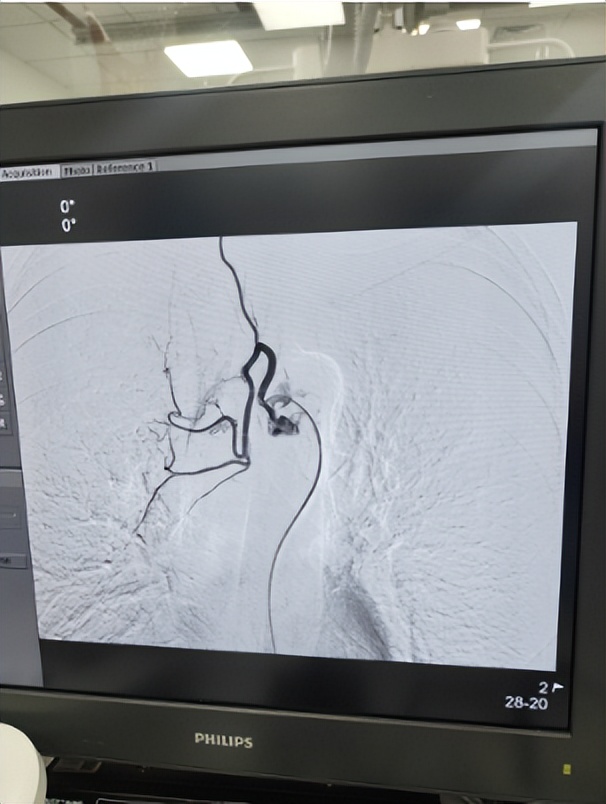

消化内科成功完成院内首例布加综合征介入术

消化内科收治一名明确肝硬化患者,术中造影发现患者为完全型膜型布加综合征,需要“破膜”穿刺,这是介入治疗中的最具挑战性步骤,有心脏破裂猝死风险。消化介入亚专业团队在南京鼓楼医院张明教授的指导下,成功穿刺破膜后逐级进行球囊扩张,术后患者下腔静脉压力差由术前10mmHg降为2mmHg,下腔静脉及肝静脉血顺利回流心脏。

近年来,消化内科积极响应院领导提出的“内科介入化”发展方针,在时昭红主任的统筹规划下,消化内科在常规开展EUS、ERCP、ESD、小肠镜等国内先进的内镜诊疗技术同时,积极打造放射介入亚专业组。2019年选送骨干易宏锋副主任医师到南京鼓楼医院进修消化介入。2020年,易宏锋学成归来,先后独立开展了经颈静脉肝内门体分流术(TIPS)、球囊阻断逆行经静脉闭塞术(BRTO)、经颈静脉肝活检(TJLB)、肝静脉压力梯度测定(HVPG)、肝癌动脉灌注化疗栓塞治疗(TACE)等国内先进介入诊疗项目,填补了消化内科多项介入技术空白。